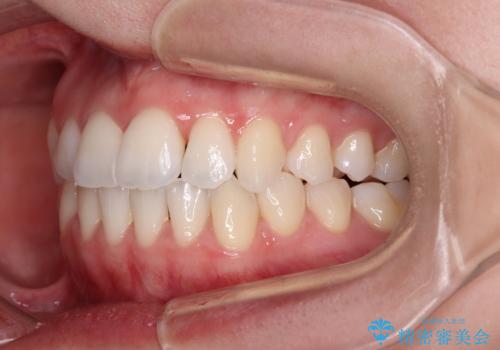

- 上下前歯のデコボコを気にして来院された患者様です。

上顎骨の横幅が狭く、奥歯は上顎よりも下顎が外側にある咬合状態でした。